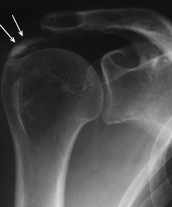

Bei der Tendinosis calcarea kommt es aus letztlich ungeklärter Ursache zu einer Kalkeinlagerung in die Sehnen der Rotatorenmanschette (Muskelmantel, der den Oberarmkopf umspannt). Häufig macht sich der Kalk nicht oder erst spät bemerkbar: entweder weil er den Raum unter dem Schulterdach, ähnlich wie beim Impingementsyndrom, einengt, oder weil sich der Kalkherd langsam auflöst. Letzteres kann einige Wochen dauern und u.U. quälende Schmerzen verursachen, die eine arthroskopische Operation erforderlich machen.